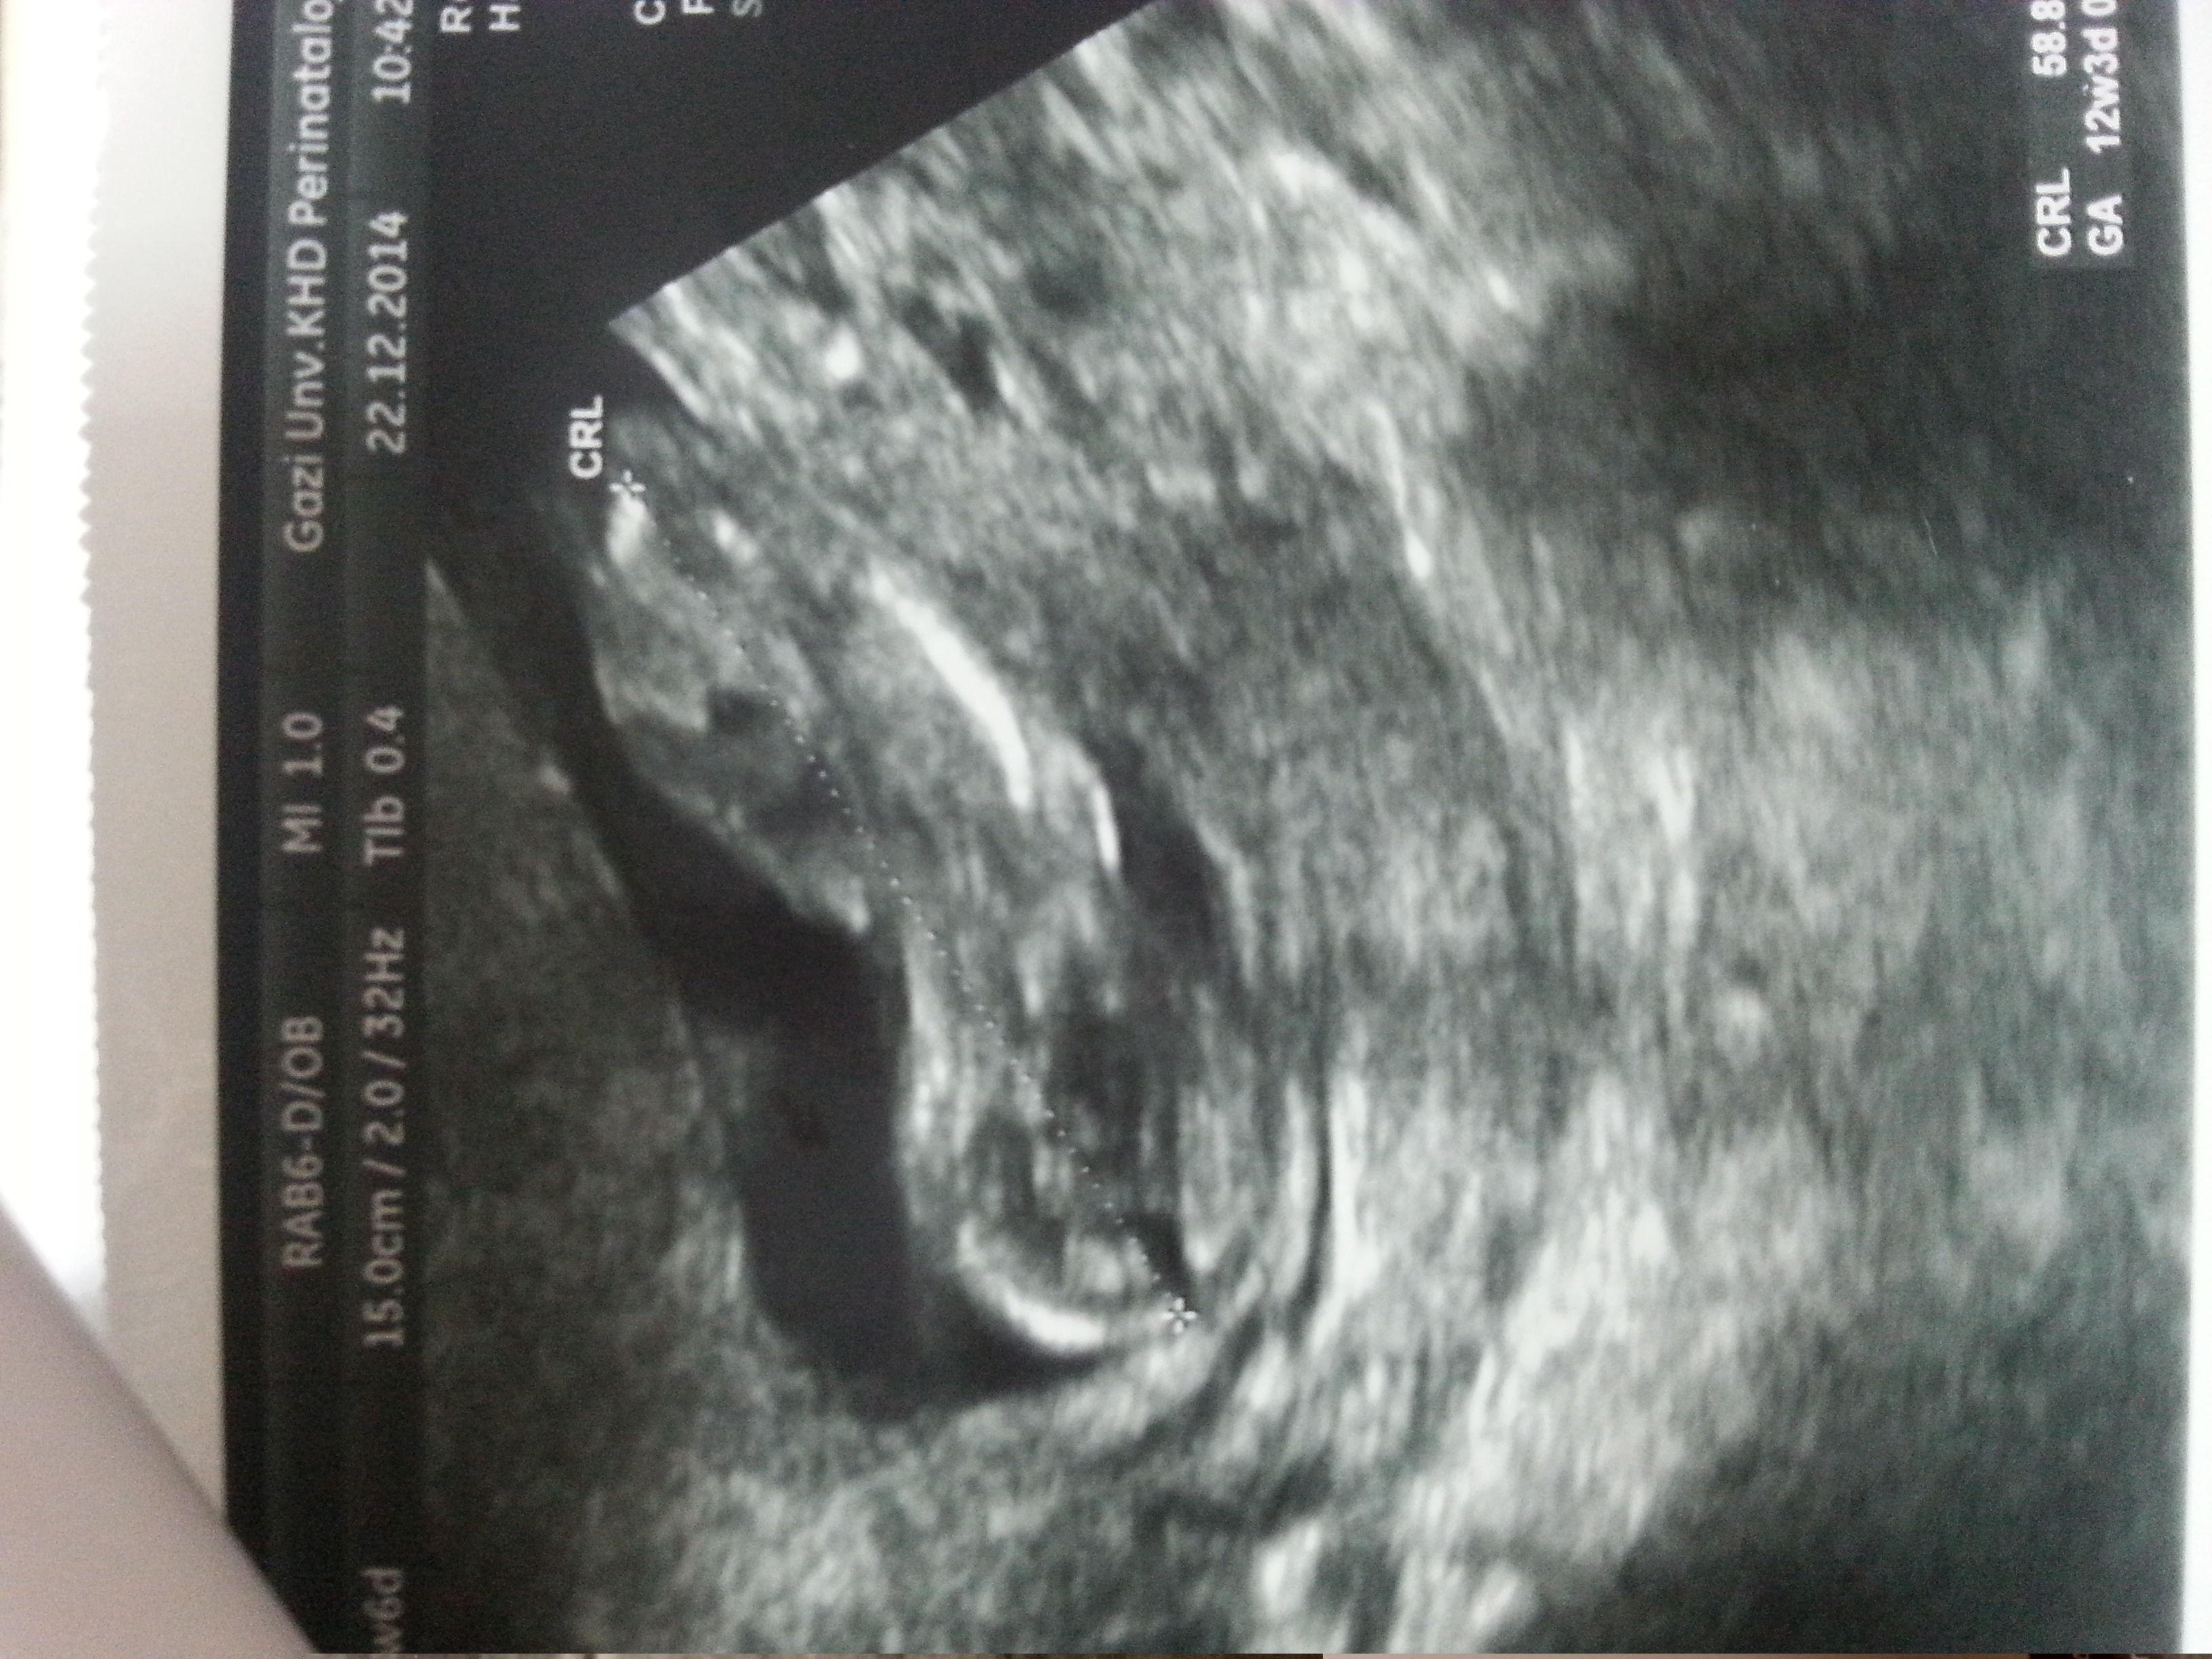

:KK15:Hanımlar benim 12+3 lük bebeme de bir yorumda bulunur musunuz rica etsem

• image.webp

image.webp

17,8 KB · Görüntüleme: 125